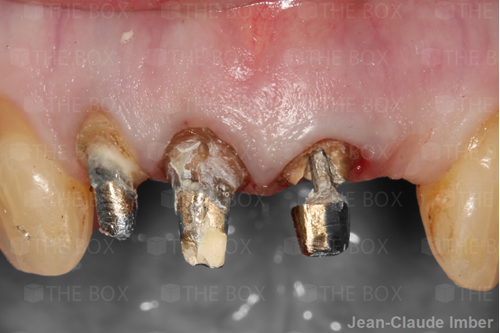

A new case was made public by Jean-Claude Imber check it out here.